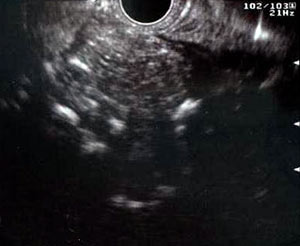

Ecoendoscopia